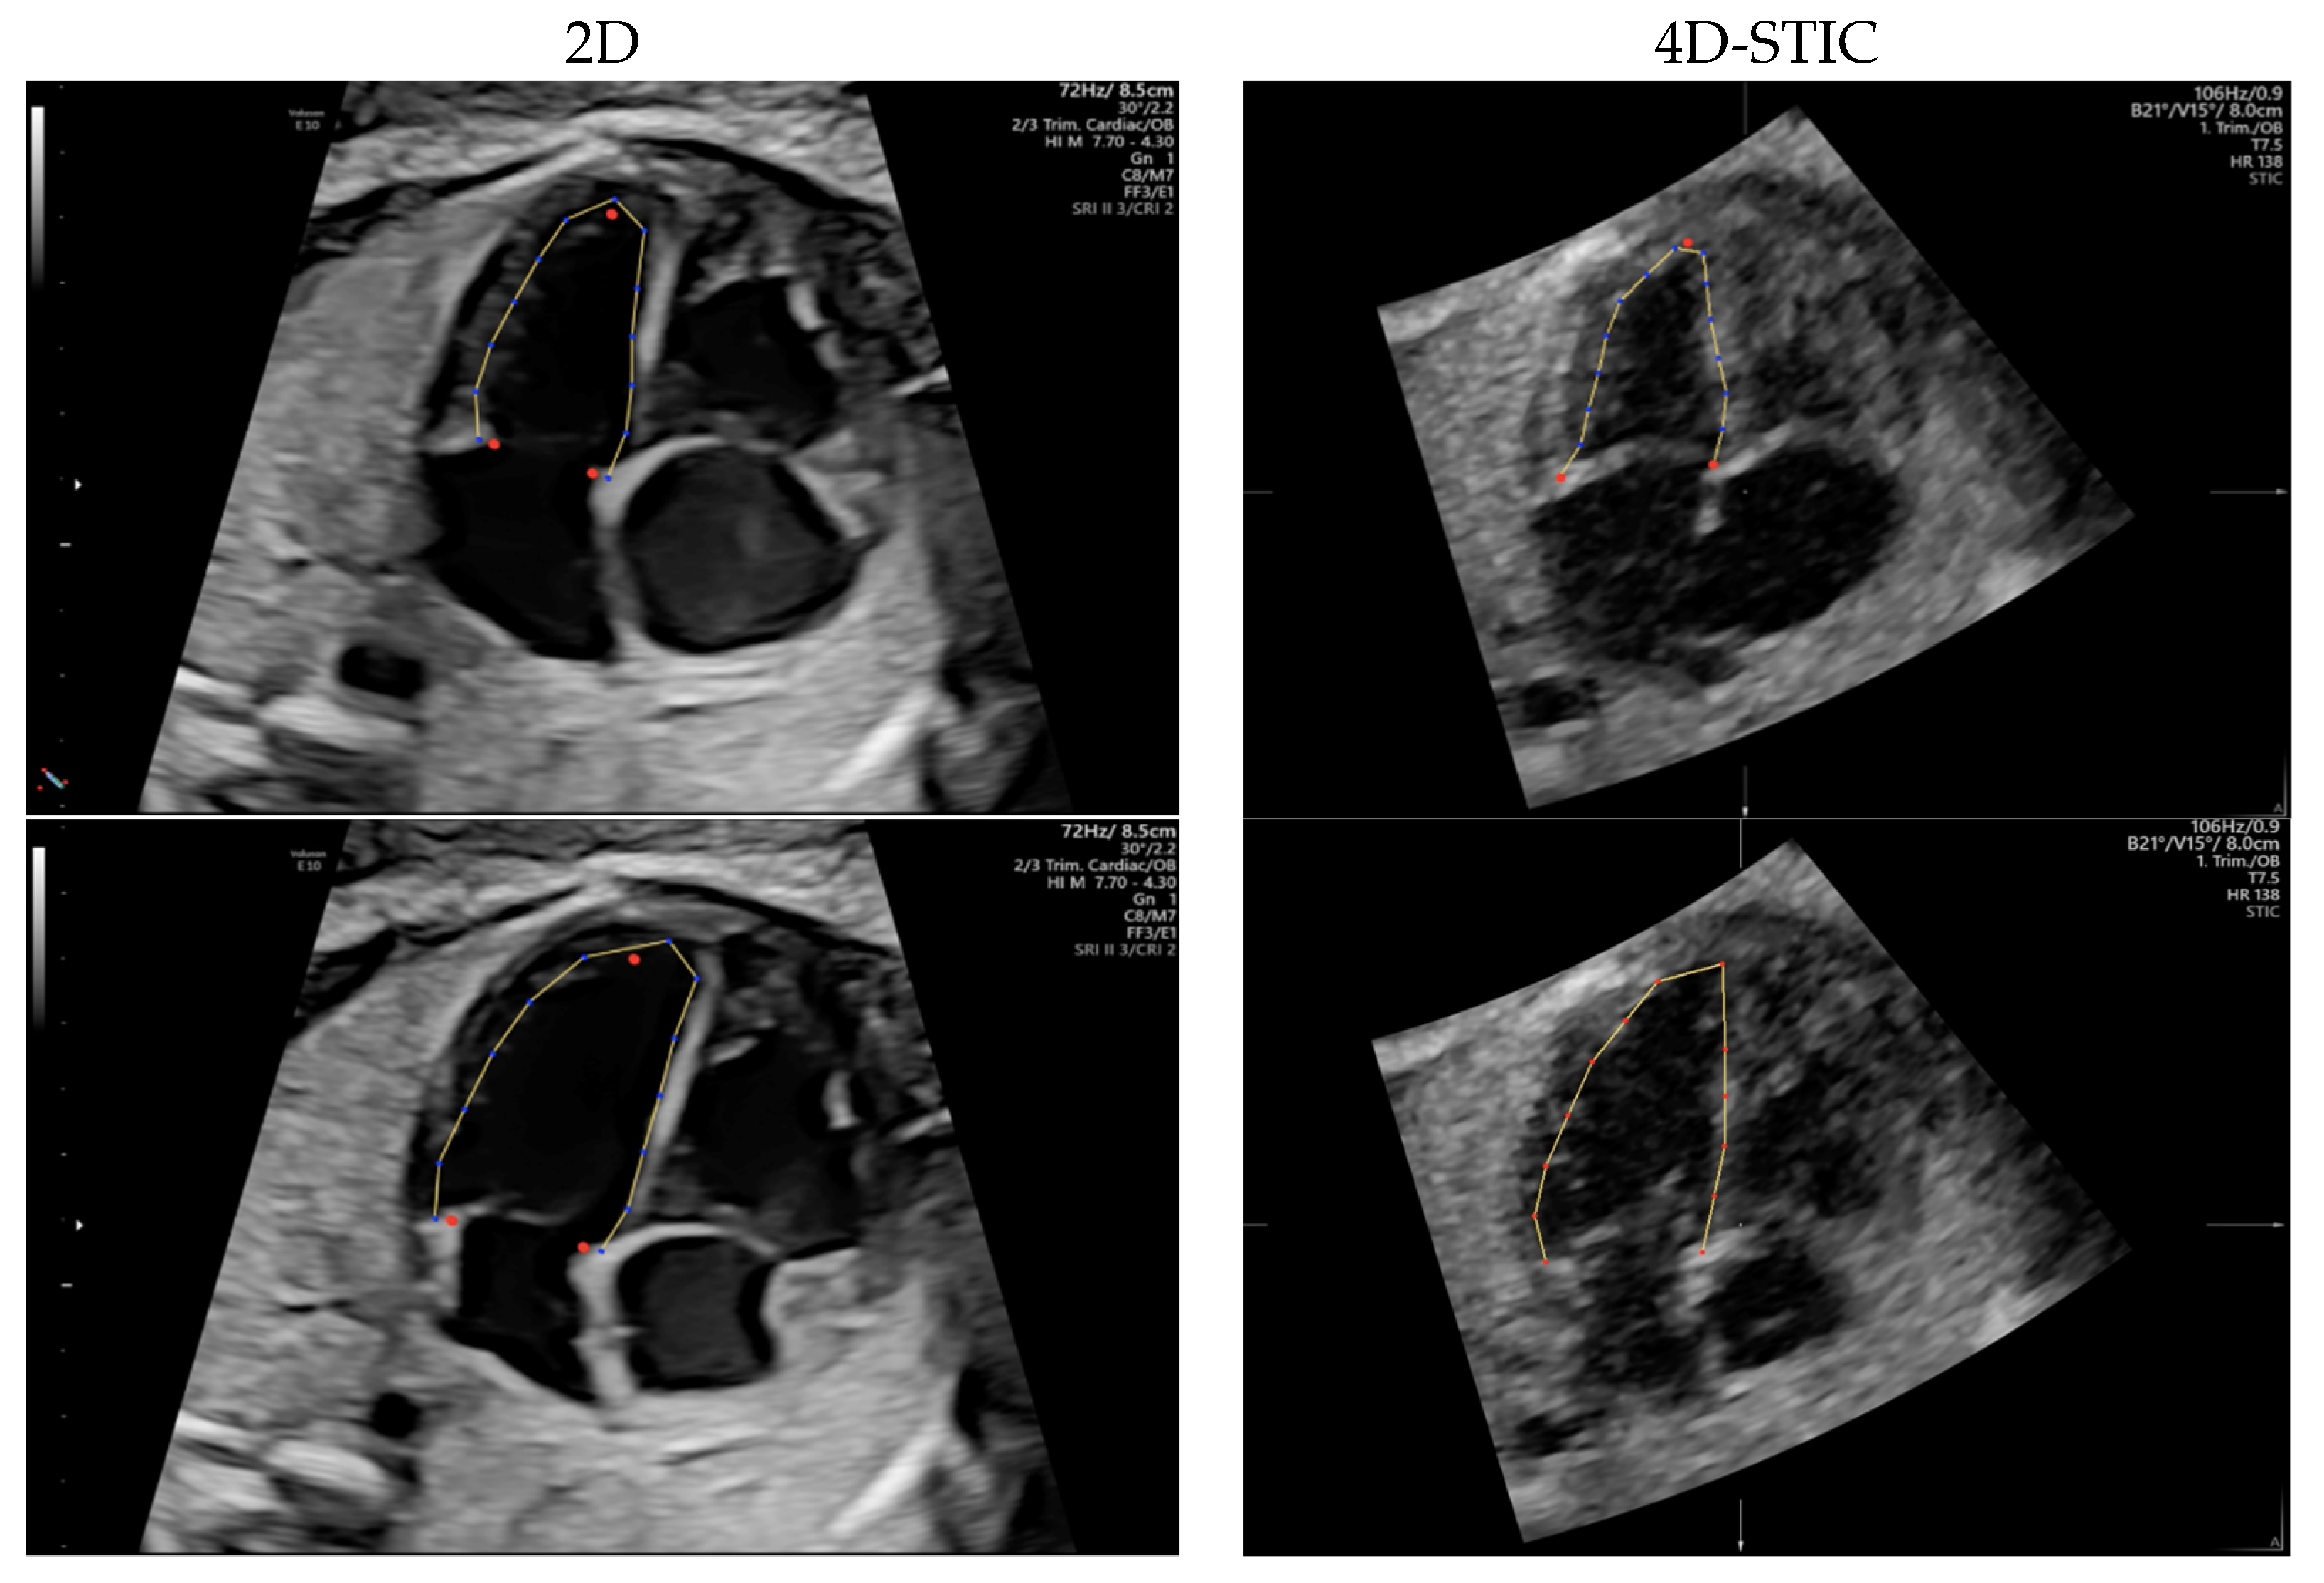

2.3. Speckle Tracking Analysis